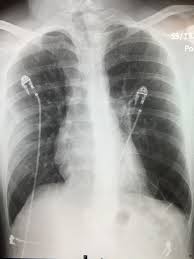

Bullous lung disease symptoms. There are several subtypes of emphysema including subcutaneous emphysema bullous. Group B GOLD 1 or 2. Most people with bullous emphysema experience shortness of breath wheezing coughing up phlegm and centralized pain in their chests especially when engaging in physical activity.

This emphysema also includes deterioration of alveolar tissue and this is basically lung tissue that makes up the walls between air sacs. Bullous Lung Disease is the most common form of emphysema. As the disease gets worse scars form and the tissue becomes stiff and thick.

Some patients suffer from nausea loss of appetite and fatigue as a. Patients frequently present with nonspecific symptoms including intermittent wheeze and cough and these are often attributed to other conditions such as asthma and smoking-related COPD especially when there is concurrent heavy smoking history. As the disease progresses you may find it increasingly difficult to breathe and engage in daily activity.

Emphysematous bullae can cause many respiratory problems including shortness of breath. Your FEV 1 is between 50 and 80. The harmful effects of tobacco smoking especially with regard to the aetiology of chronic obstructive pulmonary disease are well documented3 Large emphysematous bullae may develop usually in the context of significant tobacco exposure over many years and tend to be associated with airway obstruction reduced gas transfer factor and diffusion coefficient and evidence of centrilobular.

This is condition which is characterized by abnormal and enlarged air spaces within the lungs.